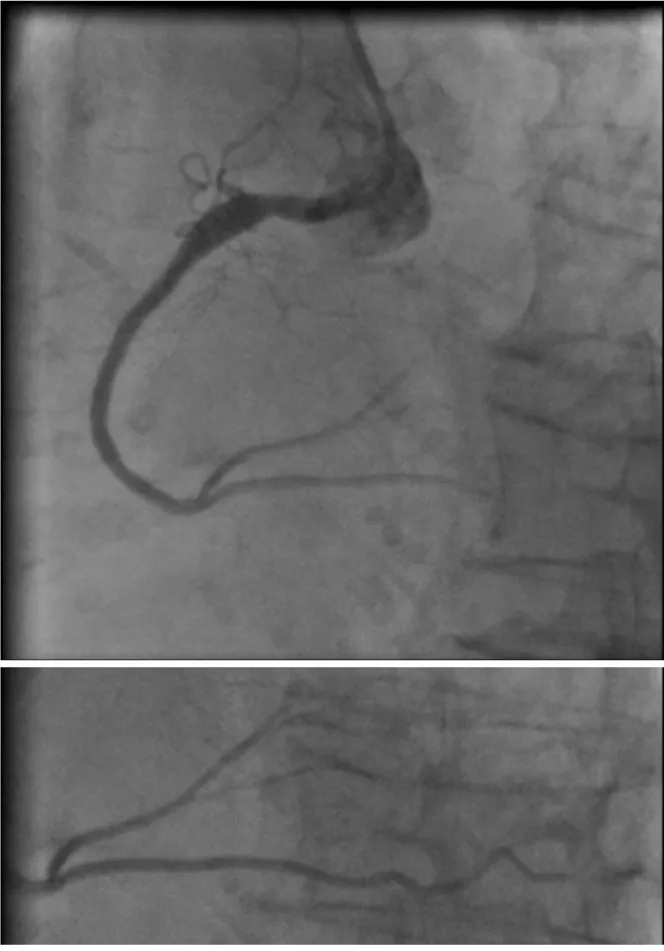

The next day a diagnostic coronary angiogram showed a right coronary artery that is large in caliber with proximal ectasia and thrombotic occlusion in the proximal segment (Figure 2).

Due to the presence of complete heart block, and even in the absence of supportive studies given her late presentation, we decided to revascularize the artery with the placement of a 3x30 drug-eluting stent and a good result and TIMI 3 flow in all branches (Figure 3).